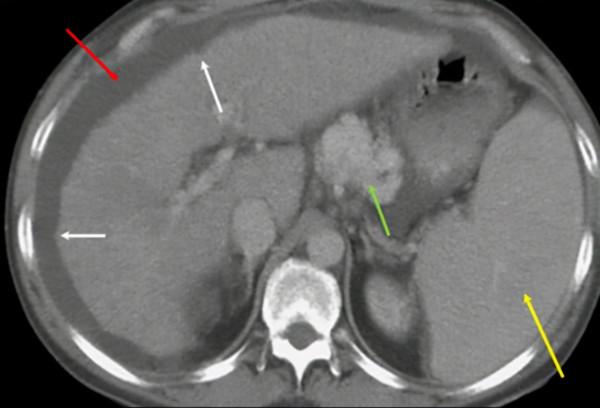

肝硬化

酗酒是美國肝硬化的第二大常見原因,僅次於丙型肝炎。當疤痕組織取代肝臟中的正常健康組織時,肝硬化就會發展。它發生在健康細胞長時間(通常是多年)受損之後,疤痕組織使肝臟結塊和堅硬,一段時間後,器官開始衰竭。疤痕組織使血液難以透過門靜脈進入肝臟。酒精對肝實質的損害導致進行性纖維化,從而產生肝臟結節狀輪廓(見圖2白色箭頭)。隨後對門靜脈血流的阻力增加誘發門靜脈高壓,可能導致脾腫大(見圖2黃色箭頭)、漏出性腹水(見圖2紅色箭頭)和靜脈曲張。圖2中顯示的計算機斷層掃描(CT)影象顯示了非常突出的食管靜脈曲張(見圖2綠色箭頭)。專門的多相造影劑增強 CT 核磁共振 (MR) 方案可用於疑似肝病的患者。